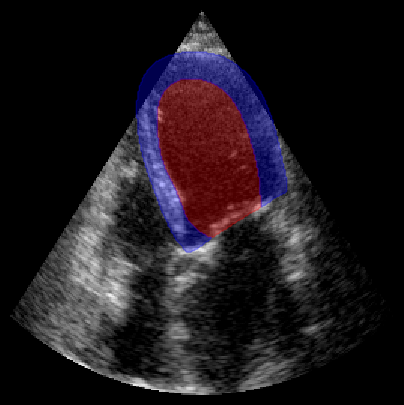

fig, ax = plt.subplots(1, 1, figsize=(5, 5))

ax.imshow(batch_np[0], cmap="gray")

plot_shape_from_mask(ax, masks[0] == 1, color="red", alpha=0.3)  # LV

plot_shape_from_mask(ax, masks[0] == 2, color="blue", alpha=0.3)  # Myocardium

plt.axis("off")

plt.show()

../../_images/notebooks_metrics_myocardial_quality_example_10_0.png

Predicted regional image quality scores:

basal_left: 4.59

mid_left: 5.21

apical_left: 3.60

apical_right: 2.37

mid_right: 2.64

basal_right: 2.99

annulus_left: 6.01

annulus_right: 4.85